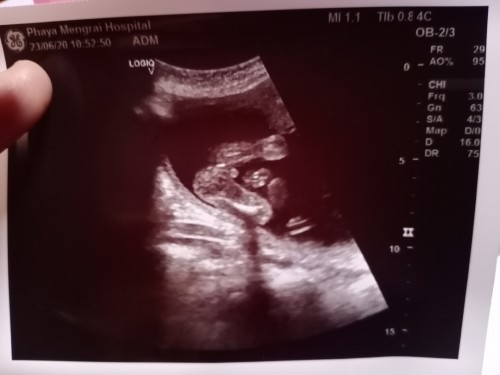

น่าจะชายค่ะเห็นเขาบอกมาว่าให้สังเกตุว่างขามีอะไรโผล่ออกมาด้วยที่ขาน้อง

ชายใช่ไหมคะแม่เหมือนเห็นจู๋ค่ะ

ใครๆก็บอกว่าชายค่ะ แต่ดูไม่เป็นเลยไม่มั่นใจค่ะ

น่าจะชายนะคะ จู๋โผล่😆